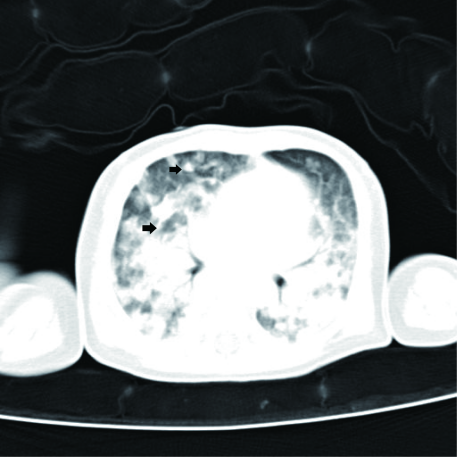

19 日齡男性患兒 1 出現(xiàn)發(fā)燒和呼吸急促及呼吸衰竭。外周血、痰、腦脊液的結(jié)核分枝桿菌培養(yǎng)為陰性,炎癥指標(biāo) CRP 為 153.04 mg/dL,降鈣素原 (PCT) 為 16.44 ng/ml,入院 2 天后外周血 Q-mNGS 檢出結(jié)核分枝桿菌(序列數(shù) 59 條,相對豐度 83.1%,病原指數(shù)(Q 指數(shù))10723.30,排位 86.03%),TAT 僅為 13 小時(shí)。隨后血液 T.SPOT 試驗(yàn)和痰標(biāo)本 Xpert MTB/RIF 試驗(yàn)陽性,患兒及母親也呈現(xiàn)出結(jié)核感染影像學(xué)特征,基于此臨床診斷該患兒為先天性結(jié)核病,并進(jìn)行針對性治療后患兒恢復(fù)正常。?

圖 1 患兒的胸部 CT 結(jié)果